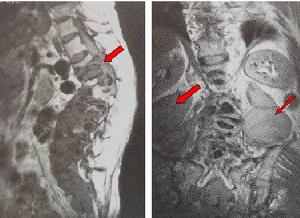

本病大部分可出現急性腹痛,神經根性痛,髖關節痛,或嚴重敗血症等症狀。在一些病例中,炎性細胞浸潤椎旁軟組織可形成椎旁膿腫,表現為受累椎體、椎間盤及相鄰椎體的椎旁軟組織增厚,橫斷面病變呈環繞椎體的軟組織腫塊影,膿腫範圍累及硬膜外間隙可致使硬膜囊腹側受壓呈弧形改變,嚴重時累及脊髓,甚至脊髓嚴重受壓變形,引起截癱。

(3)、MRI表現為椎體呈長T1、長T2異常信號,FLAIR序列及增強掃描對明確診斷有很大幫助;

椎體及附屬檔案破壞變形,呈長T1、長T2信號改變,椎體邊緣信號異常部分與正常分界模糊,椎間盤失去正常形態及信號,呈不同程度的腫脹增厚或破壞、碎裂,椎間隙有不同程度狹窄,呈長T1、更長T2改變,椎前、椎旁軟組織腫脹,T1WI上與肌肉組織相似,T2WI上信號更高,邊緣有線樣低信號影可能為膿腫壁,增強掃描後,受累椎體、間盤及寒性膿瘍的周邊有異常對比增強。臨床有結核病史及結核中毒症狀。